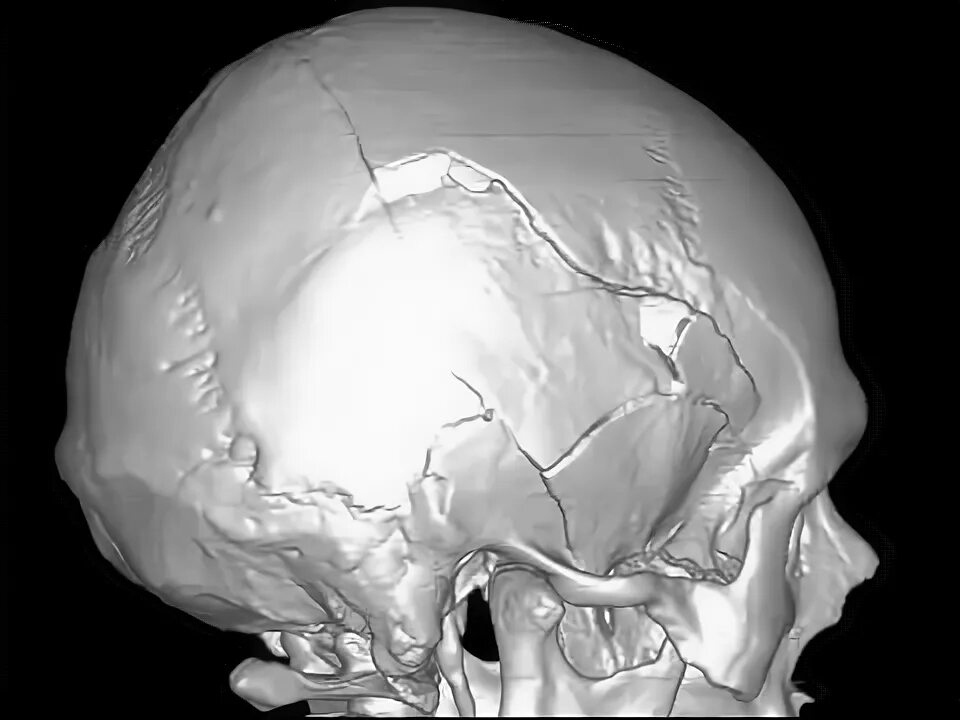

Оскольчатый перелом черепа